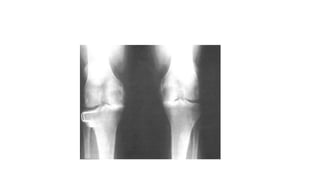

CASO CLÍNICO 2 • Nomedo paciente: J.A.F. Idade: 63 anos, Gênero: Masculino • Profissão atual: Aposentado • Profissão anterior/outras atividades: Borracheiro, aos finais de semana auxilia na barraca de feira dos filhos

Caso Clínico 2 HPMA:Após os 50 anos começou a sentir desconforto esporádico no joelho direito após as jornadas de trabalho na borracharia, mas nunca procurou orientação médica. Notou que as atividades de abaixar-se e esticar os joelhos completamente causavam dor, e quando acordava sentia dificuldade para a movimentação articular. Quando se aposentou, procurou o ambulatório de seu bairro para realizar exames de rotina e declarou a queixa em joelhos para o médico.

Caso Clínico 2 •Arco de movimento (ADM) encontra-se diminuído moderadamente a direita, com crepitação presente.

A-DIMINUIÇÃO DO ESPAÇOARTICULAR EM PLATÔ MEDIAL B -VISÃO AMPLIADA DO JOELHO DIREITO